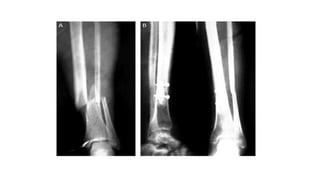

FRACTURA TIBIOPERONEA